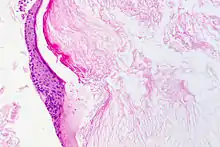

Le cholestéatome est une forme d'otite chronique avec présence d'épithélium pavimenteux stratifié dans l'oreille moyenne. Cet épithélium desquame et se kératinise (structure histologique de l'épiderme), et peut provoquer l'érosion voire la destruction des structures contenues dans et autour de l'oreille moyenne ( Histopathologie du cholestéatome)[1],[2].

Il se fait par visualisation du conduit auditif et du tympan (otoscopie). Il se manifeste par la présence d'une excroissance squameuse, le plus souvent à la partie postéro supérieure du tympan[7]. Le scanner crânien permet de visualiser l'extension et les éventuelles destructions osseuses.L'histopathologie post-opératoire est indispensable pour confirmer la nature de la lésion et celles qui lui sont associées.